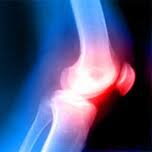

Chrupavka je tkanivo, ktoré pokrýva kĺbové konce kostí.

Je elastickej štruktúry a umožňuje výrazné zníženie trenia kontaktných plôch. Chrupavka sa neustále prestavuje a dochádza tak k reparácii jej poškodenia. Zvýšená záťaž a nadmerné poškodzovanie chrupavky môže prekročiť regeneračnú schopnosť a znižuje sa jej výška. Kosť pod chrupavkou reaguje zvýšenou bolestivosťou. Dráždenie kĺbovej výstelky vedie ku zmnoženiu tekutiny v kĺbe, k obmedzeniu hybnosti, prípadne k blokádam a pod.

Degeneratívne zmeny na chrupavke sú prvými liečiteľnými príznakmi degeneratívneho ochorenia pohybového aparátu. Ak nezabránime poškodeniu chrupavky včasnou či ešte lepšie preventívnou liečbou, poškodenie kĺbu bude časom nevratné.